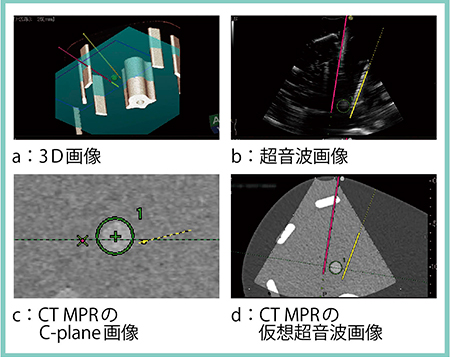

さらに,上記のシミュレーション画像をナビゲータとして使用することもできる。特に,腫瘍の最大断面を含んで表示されるMPRのC-plane画像(穿刺方向と直交する断面)が非常に重要な役割を果たす。図2は,ファントムに対する実際の穿刺の様子であるが,3D画像上に穿刺ガイドラインが描出され,穿刺方向があらかじめわかるようになっている(図2 a)。また,C-plane画像上には穿刺した電極針の履歴が残るので(図2 c),2本目,3本目の電極針をバランス良く配置することができる。このような機能は従来の穿刺システムにはないものであり,きわめて有用である。

図2 ナビゲータとしての3D Sim-Navigator